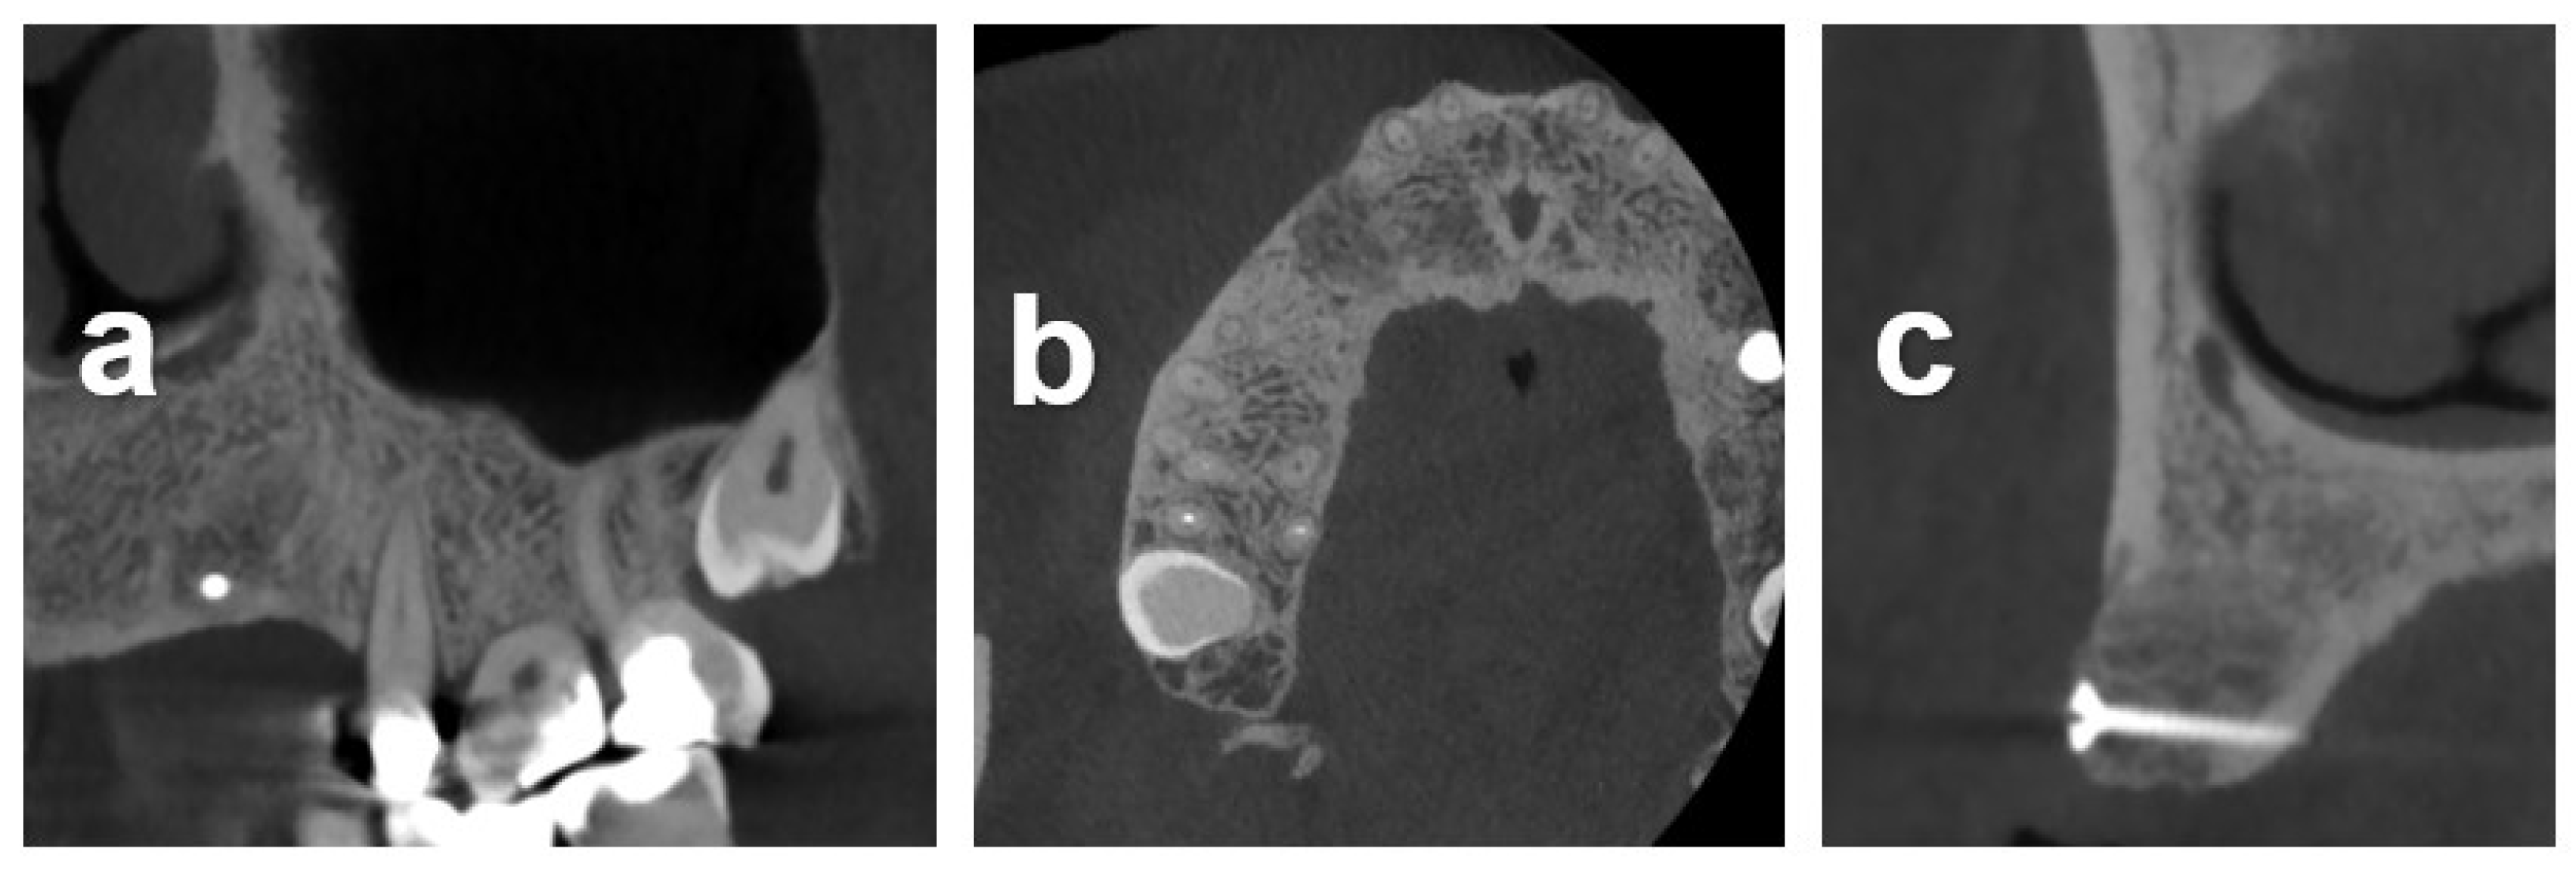

2.7.1. Case 1

2.7.2. Case 2

2.7.3. Case 3

3.2. Radiometric Assessment

| Baseline | 3.0 | 2.0 | 2.0 | 5.0, 8.4 | 3.0 | 3.0 (2.3 to 4.5) | 2.0–8.4 |

| 5-month follow-up | 8.0 | 10 | 11.5 | 12.0, 12.5 | 10 | 10.8 (10 to 11.9) | 8.0–12.5 |

| Horizontal Gain ‡ | 5.0(×9.0) ‡ | 8.0(×9.0) | 9.5(×8.0) | 7.0 (×11.0), 4.0 (×11.0) | 7.0(×5.2) | 7.0 (5.5 to 7.8) | 4.0–9.5 |